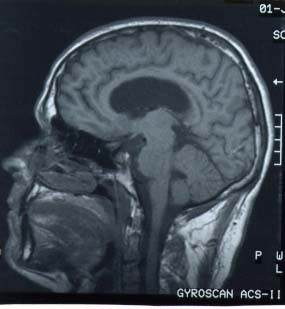

Une coupe mdio-sagittale de la fosse

postrieure montre lÕaspect grossirement triangulaire de la loge occupe par

le cervelet. Cet espace est dlimit par: le ple occipital en haut, le tronc

crbral en avant et lÕcaille occipitale en bas.

Imag. 02 - Coupe mdio-sagittale de lÕencphale (CHU Rabat) |

Ces limits correspondent aux trois faces du

cervelet : une face antrieure ou ventrale (c) rattache au tronc crbral

(tc), et deux faces dorsales, dlimite par une crte, la face suprieure (a)

moule contre la tente dure-mrienne qui la spare du cerveau, et la face

infrieure (b) applique contre le squelette occipital.